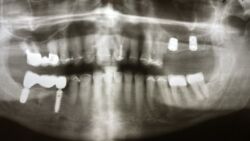

Langjähriger Kieler Patient mit Zahnentfernungen und Implantationen

Heute wurden die Zähne 25 und 28 osteotomiert, denn so richtig zum Anfassen mit einer Zahnge war da nichts mehr.

Dann wurde in die Alveole 25 und in den Bereich 27 jeweil ein Implantat inseriert. In regio 25 im Sinne eines Internen Sinusliftes mit minimaler Anhebung der Kieferhöhlenmembran.